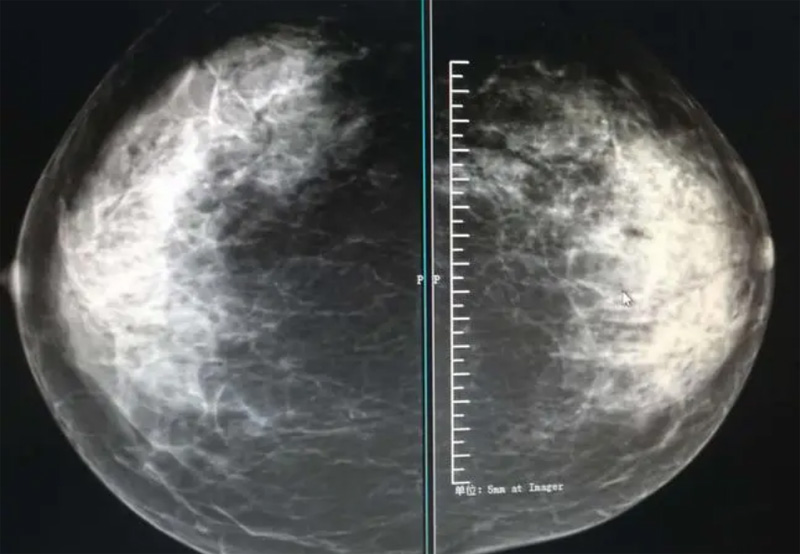

攝影診斷規(guī)范乳腺DR有頭尾位及內(nèi)外側(cè)斜位診斷概念和診斷術(shù)語

乳腺DR的檢查中為了讓乳腺相關(guān)疾病的篩查需要更高質(zhì)量的檢查圖像。檢查前期的準備工作非常重要。醫(yī)生跟病患的有效溝通。要跟檢查者說明檢查過程,特別是體位跟擠壓乳房帶來的不適應(yīng)。放松心情,檢查過程中得到充分的合作。正確的擺正位置乳腺DR可以拍攝到更優(yōu)質(zhì)清洗高質(zhì)量的X線圖像。乳腺DR檢查需要再月經(jīng)后檢查,但是對病癥明顯的就不受這個限制。

乳腺DR攝影體位有頭尾位及內(nèi)外側(cè)斜位,

乳房在片子的中央,乳頭切線位,可見小部分胸大肌,內(nèi)側(cè)乳腺組織應(yīng)全部包括在片中,外側(cè)乳腺組織盡可能包括在片中。一張好的MLO位圖像顯示如下:乳房被推向前上,乳腺實質(zhì)充分展開,胸大肌可見,較松弛,下緣達到乳頭水平,乳頭在切線位,部分腹壁包括在片中,但與下部乳腺分開,絕大部分乳腺實質(zhì)顯示在片中。乳腺組織外緣可見乳頭的輪廓;乳腺后方的脂肪組織被很好地顯示出來,乳房無皺褶。對于CC位及MLO位顯示不良或未包全的乳腺實質(zhì),可以根據(jù)病灶位置的不同選擇以下體位:外內(nèi)側(cè)位(LM)、內(nèi)外側(cè)位(ML)、內(nèi)側(cè)頭尾軸位(MCC)、外側(cè)頭尾軸位(LCC),尾葉位(CLEO)及乳溝位。在臨床實踐中,對于常規(guī)體位上發(fā)現(xiàn)的異常改變,可以進一步采取一些特殊的攝影技術(shù),包括局部加壓攝影、放大攝影或局部加壓放大攝影技術(shù)。

必須指出的是,美國放射學會提出的乳腺影像報告和數(shù)據(jù)系統(tǒng)(Breast Imaging Reporting and Data System, BI-RADS)將乳腺分為4型:脂肪型(乳腺內(nèi)幾乎全部為脂肪組織,腺體組織占25%以下)、少量腺體型(乳腺內(nèi)散在腺體組織,大約占25%~50%)、多量腺體型(乳腺呈不均勻致密表現(xiàn),腺體組織大約占51%~75%)、致密型(乳腺組織非常致密,腺體組織占75%以上)。這種分型的主要意義在于說明X線對不同乳腺類型中病變檢出的敏感性不同,對發(fā)生在脂肪型乳腺中病變的檢出率很高,而對發(fā)生在致密型乳腺中病變的檢出率則有所降低,臨床醫(yī)師了解這一點很重要。